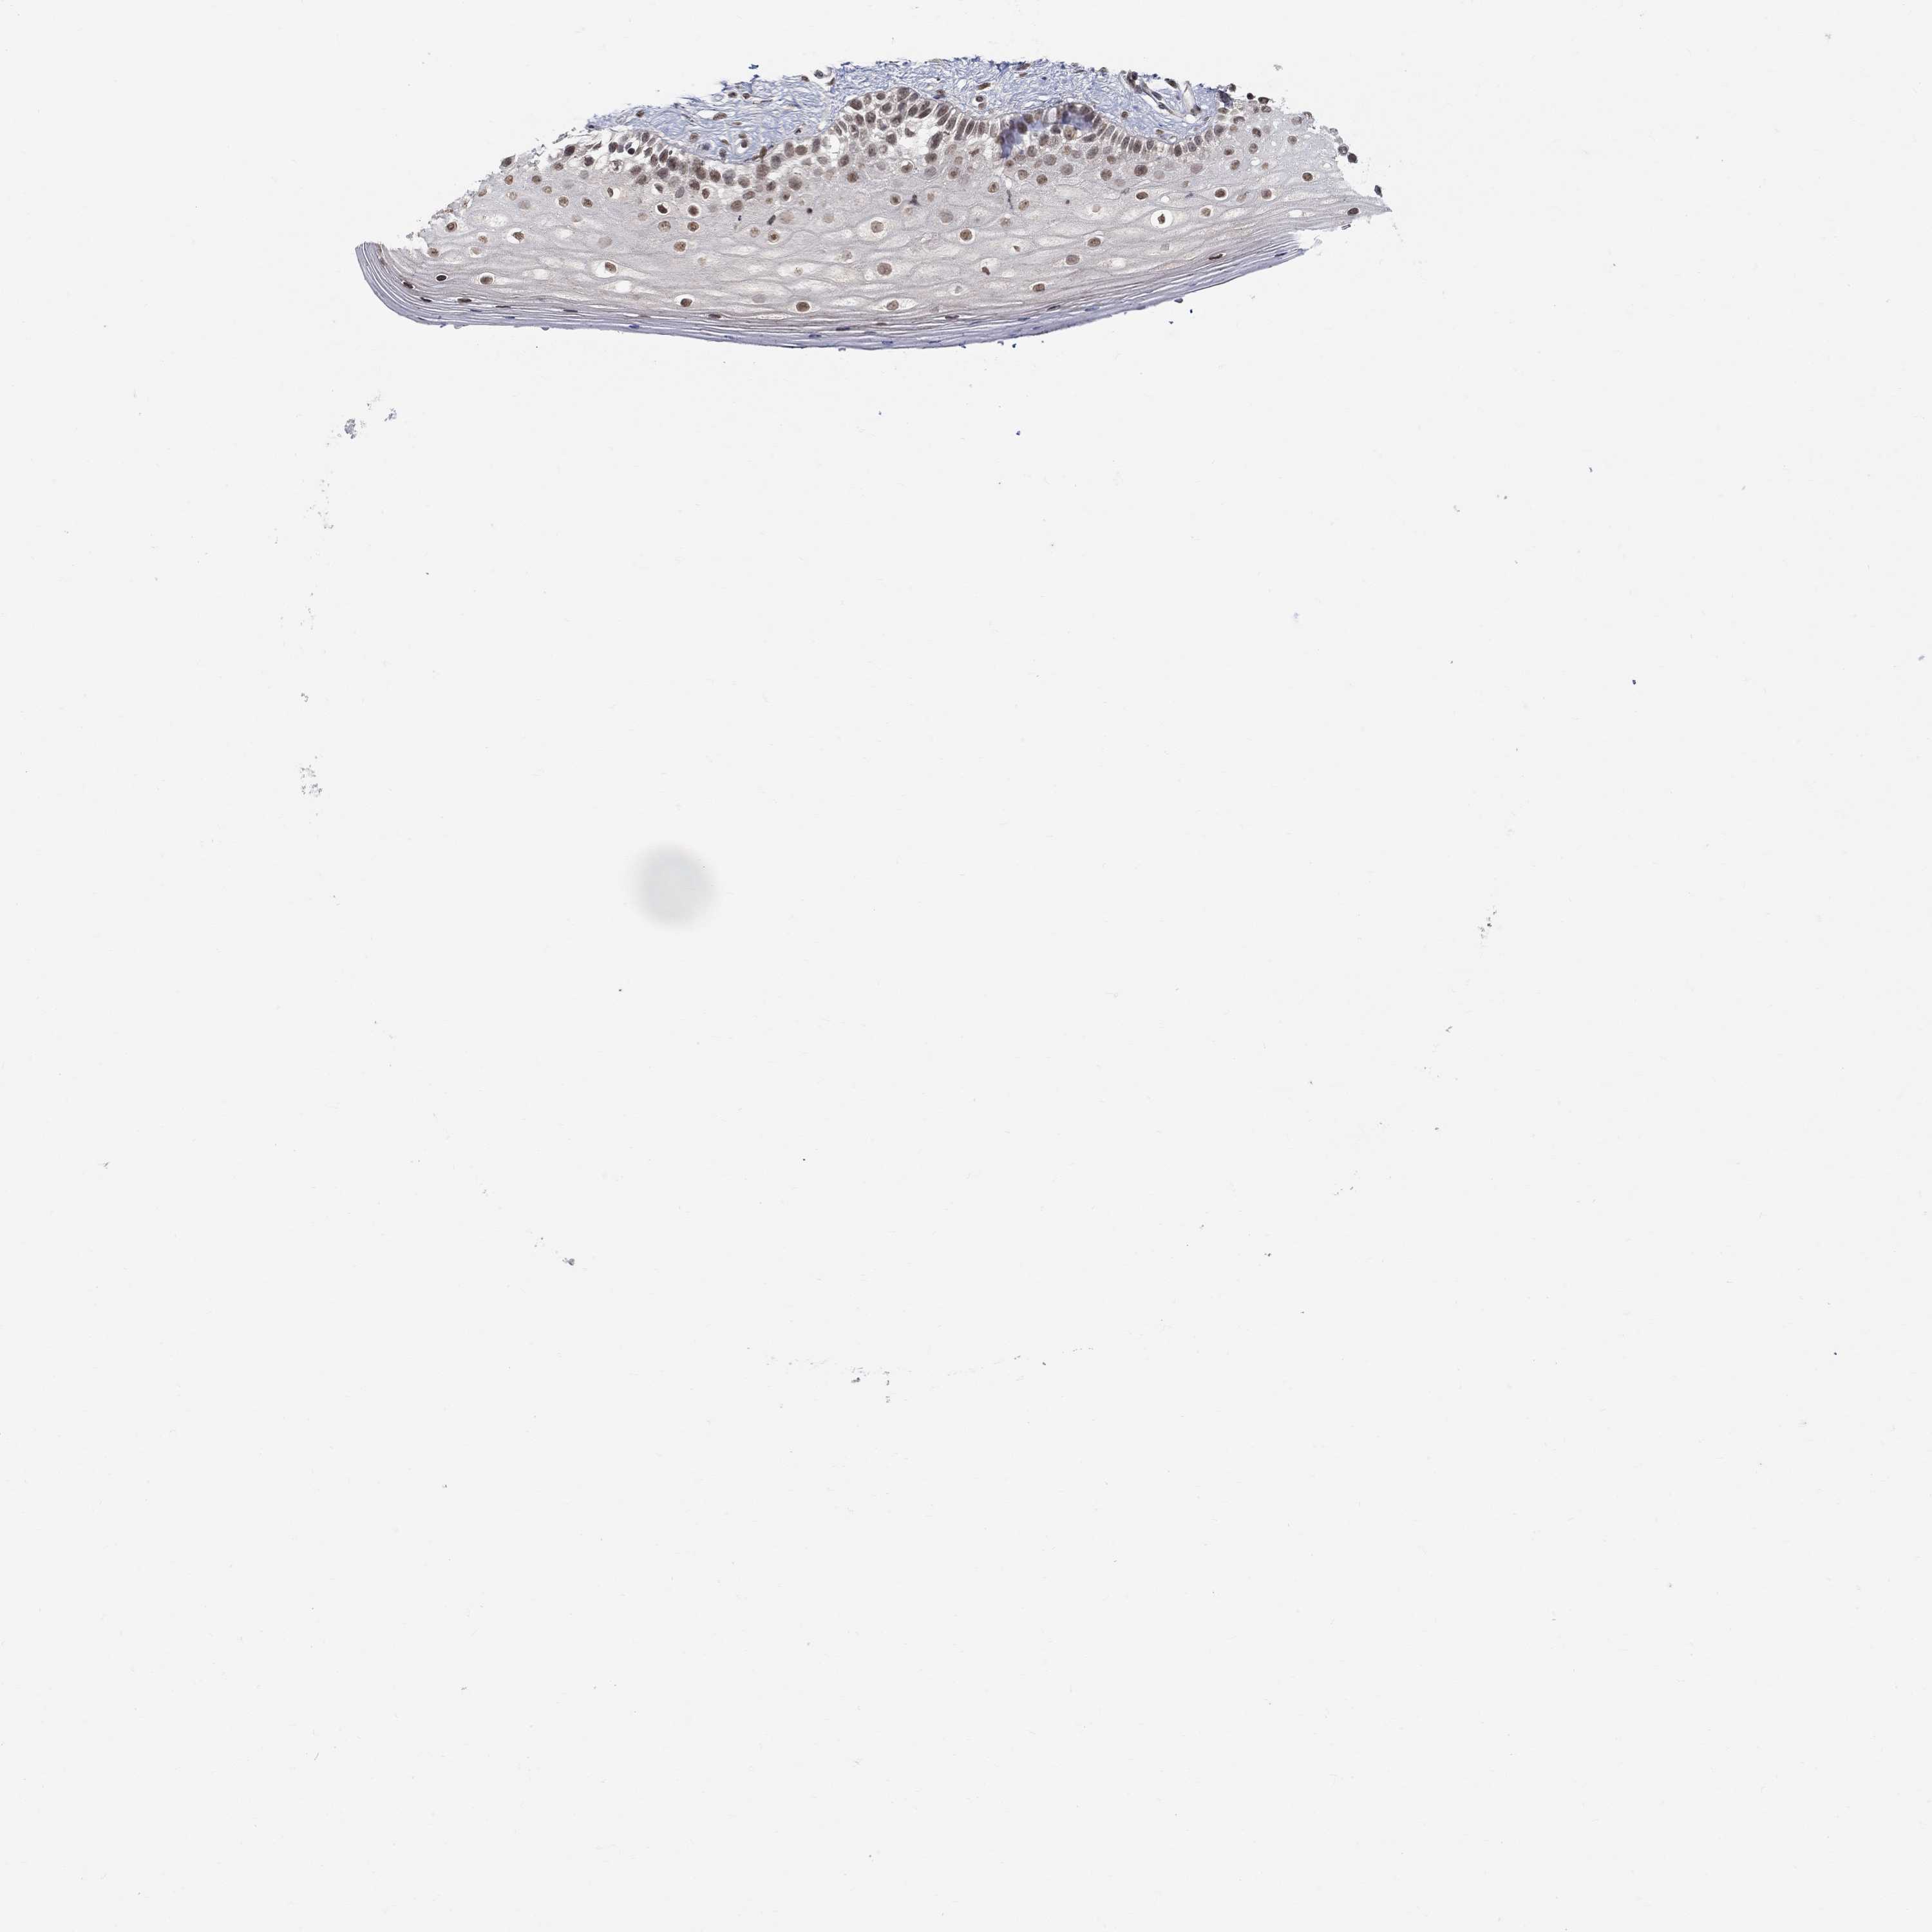

VAGINA - Antibody stainingi

Antibody staining in the annotated cell types in the current human tissue is reported as not detected, low, medium, or high, based on conventional immunohistochemistry profiling in selected tissues. This score is based on the combination of the staining intensity and fraction of stained cells.

Each image is clickable and will lead to virtual microscopy that enables deeper exploration of all samples and also displays staining intensity scores, fraction scores and subcellular localization as well as patient and tissue information for each sample.

Antibody HPA075652

Squamous epithelial cells Low